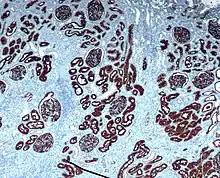

Immunohistokemisk farvning bruges meget til at diagnosticere unormale celler, som dem fundet i kræft-svulster. Specifikke molekylære markører er karakteristiske for afgrænsede cellulære tilstande så som vækst eller celledød (apoptose). IHC bruges desuden ofte i grundforskning for at kunne forstå fordelingen og placeringen af biomarkører og forskelligt udtrykte proteiner i forskellige dele af biologisk væv.

For at visualisere (tydeliggøre) en antistof-antigen reaktion konjugerer man oftest et antistof (der reagerer med antistoffet der detekterede antigenet) med et enzym så som peroxidase. Dette enzym kan så katalysere en farveskabende reaktion under tilstedeværelse af et såkaldt kromogen. Alternativt kan antistoffet blive markeret med et fluorophore-stof, så som fluorescein eller rhodamine (se immunofluorescens).